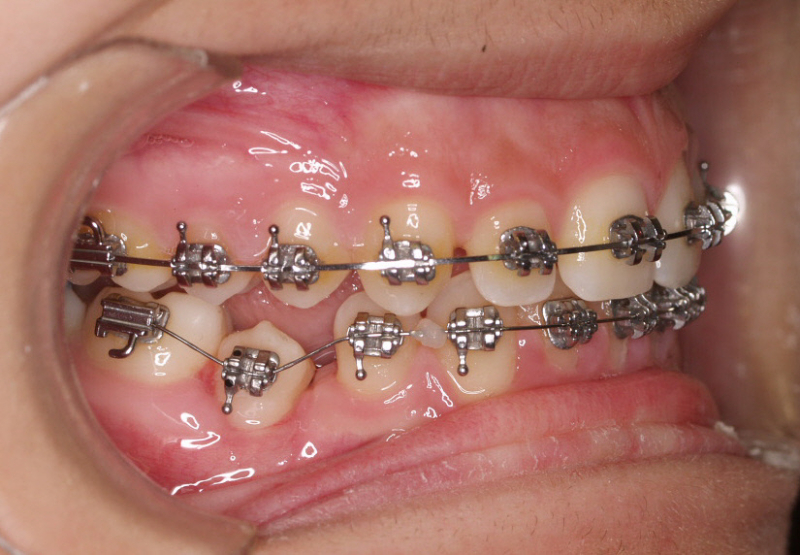

Premolar mandibular incluido + fenestración

45 incluido